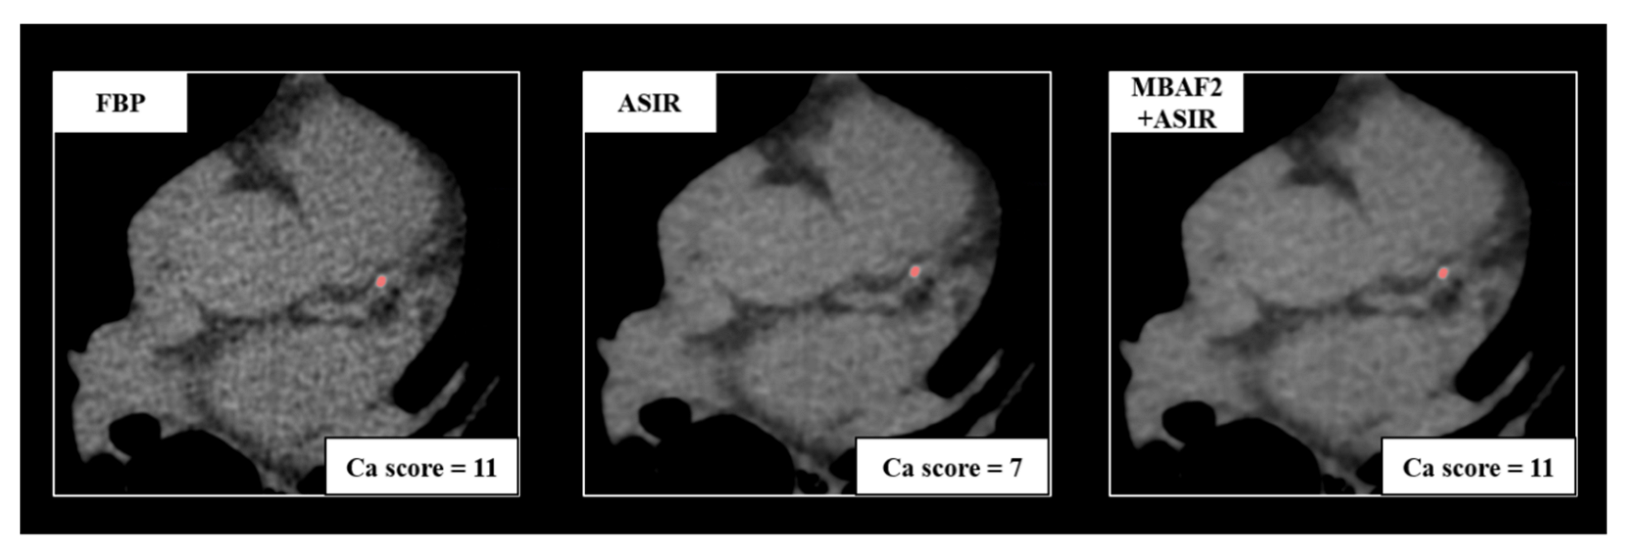

We measured CACS based on the Agatston method on axial series with the dedicated built-in software of Philips IntelliSpace Portal (Heartbeat-CS, Philips Healthcare, Best, Netherlands) [16]. With this semi-automatic method, the software can detect voxels above a density of 130 Hounsfield units and an area of 1 mm2. Calcifications were identified on all three reconstructions (FBP, ASIR-CV, and MBAF2+ASIR-CV) by a trained radiologist with 6 years of experience in coronary CT. Patients were classified into the following CV risk categories based on the overall Agatston scores: 0: no identifiable calcification; 1–10: minimal calcification; 11–100: mild calcification; 101–400: moderate calcification; 400<: severe calcification. We analyzed the risk classification of each patient based on the three reconstruction methods and determined the number of patients who needed reclassification to a different CV risk group due to the utilization of ASIR-CV or MBAF2+ASIR-CV. We demonstrate a representative case of reclassification on a 61-year-old patient in Figure 1.

Figure 1.

A representative example of a 61-year-old female patient with atypical chest pain. Acquisition acquired at routine dose reconstructed with FBP, ASIR-CV, and MBAF2+ASIR-CV. Both techniques markedly decreased image noise; however, the utilization of ASIR-CV resulted in the reclassification of the patient into a smaller cardiovascular risk group. FBP: filtered back projection; ASIR: adaptive statistical iterative reconstruction; MBAF2: model-based adaptive filter.